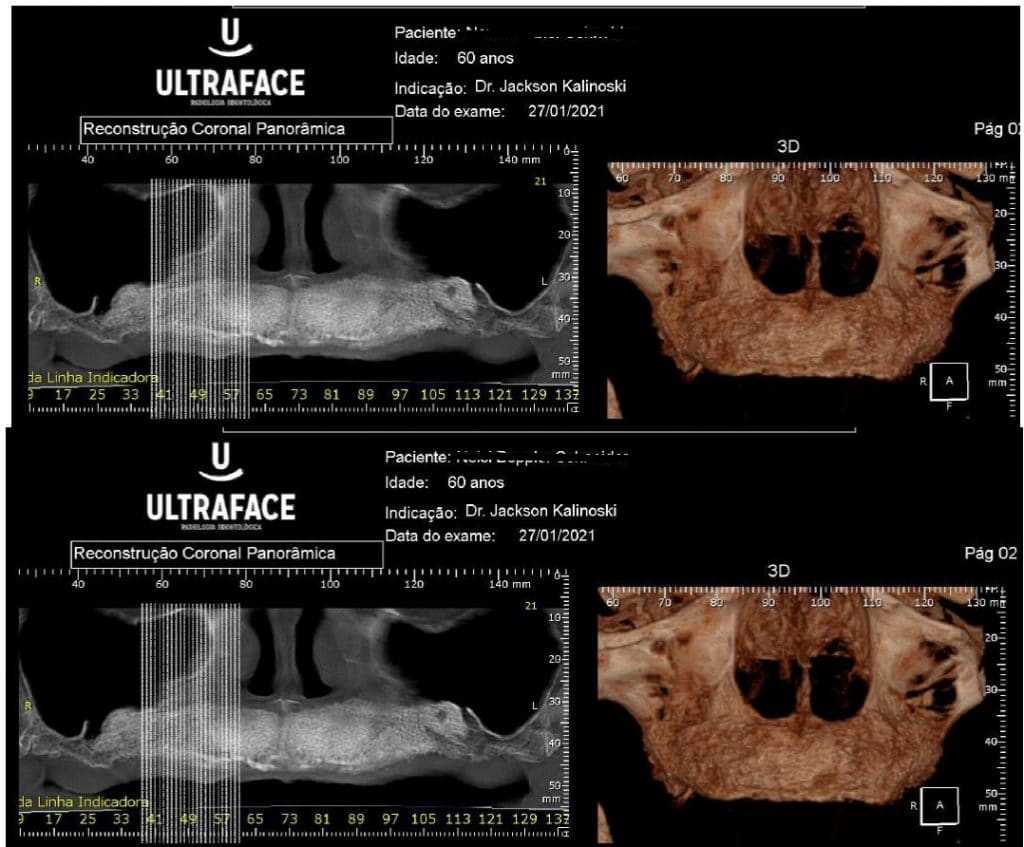

Olá colegas, aqui está um caso didático de reconstrução óssea total da maxila, levantamento do seio maxilar bilateral e bloqueio espesso com aplicação do conceito de PRF e Biotensigrity.

SEM tela, SEM parafusos, SEM membranas de colágeno. Substitua apenas osso aloplástico e sangue.

Após 6 meses de maturação óssea e implantes instalados com torque médio de 35 N / cm2.